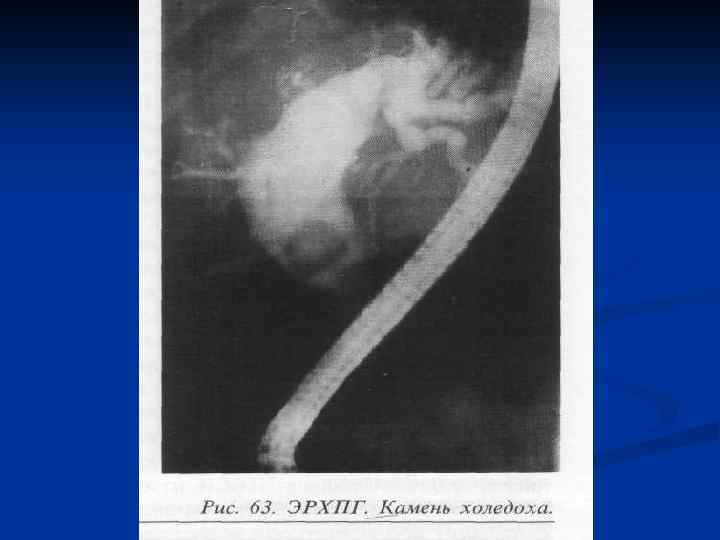

ЭРХПГ. Холедохолитиаз.

ЭРХПГ. Холедохолитиаз.